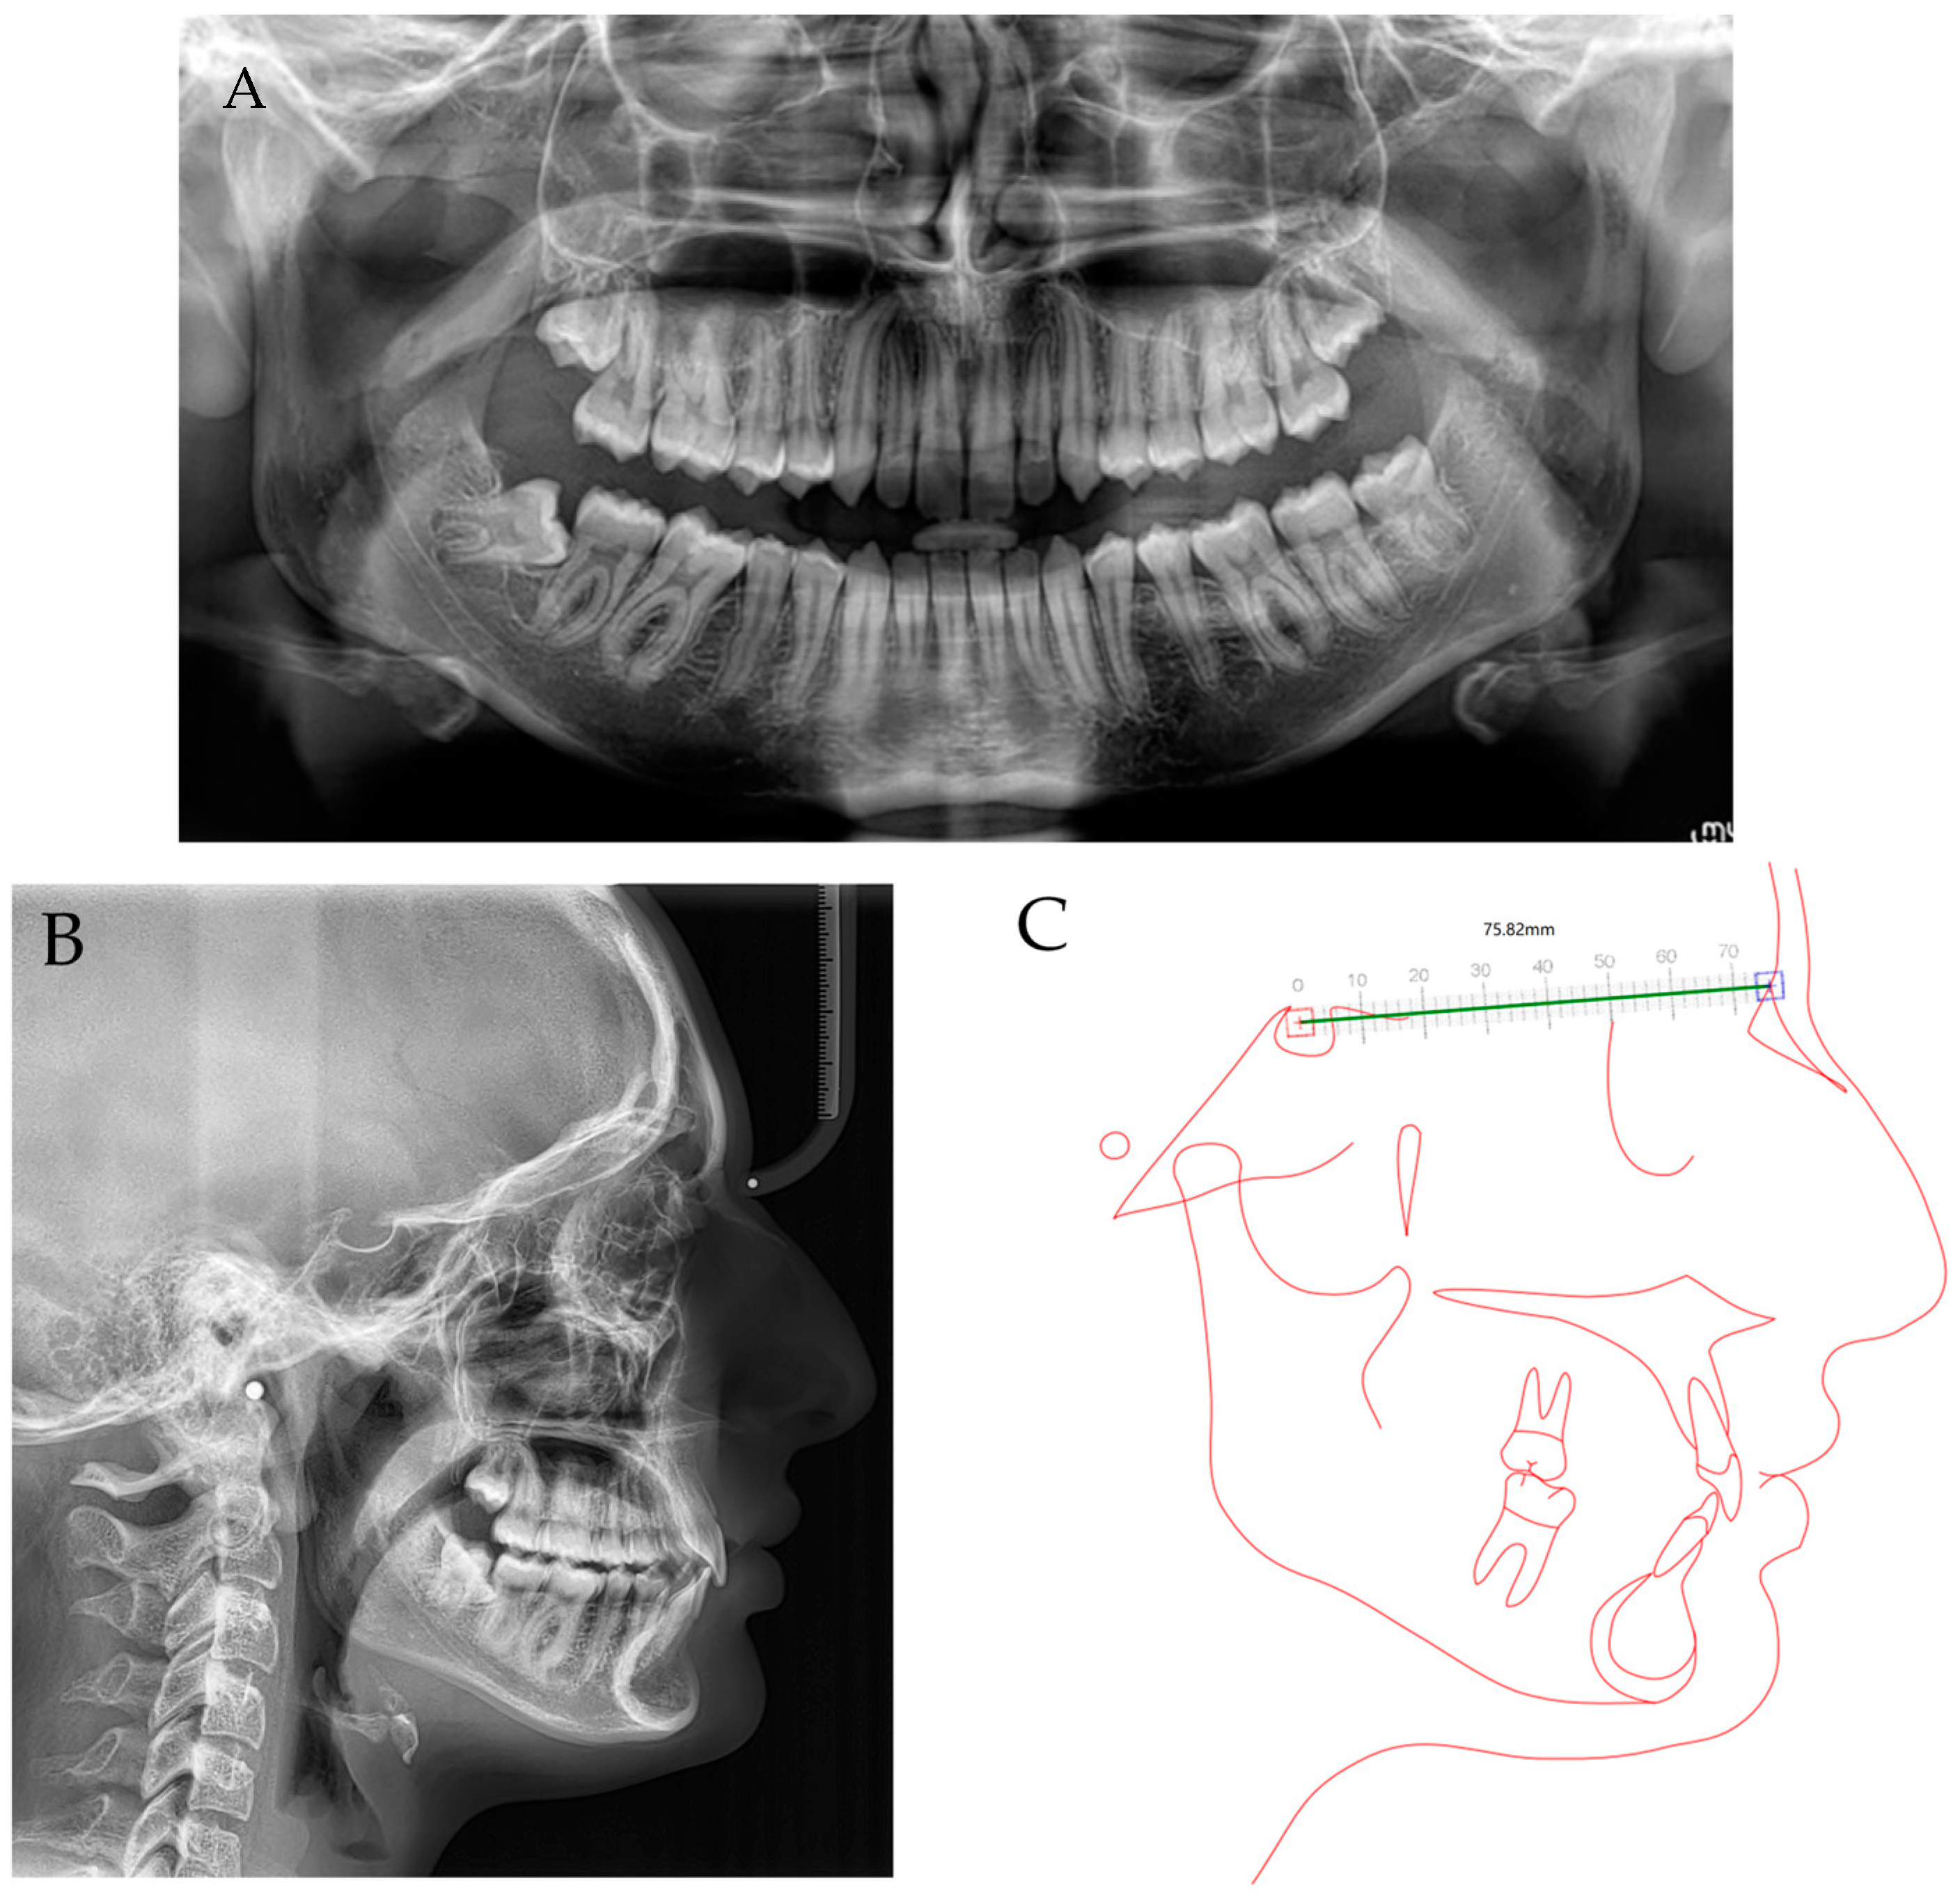

2.1. Diagnosis and Etiology